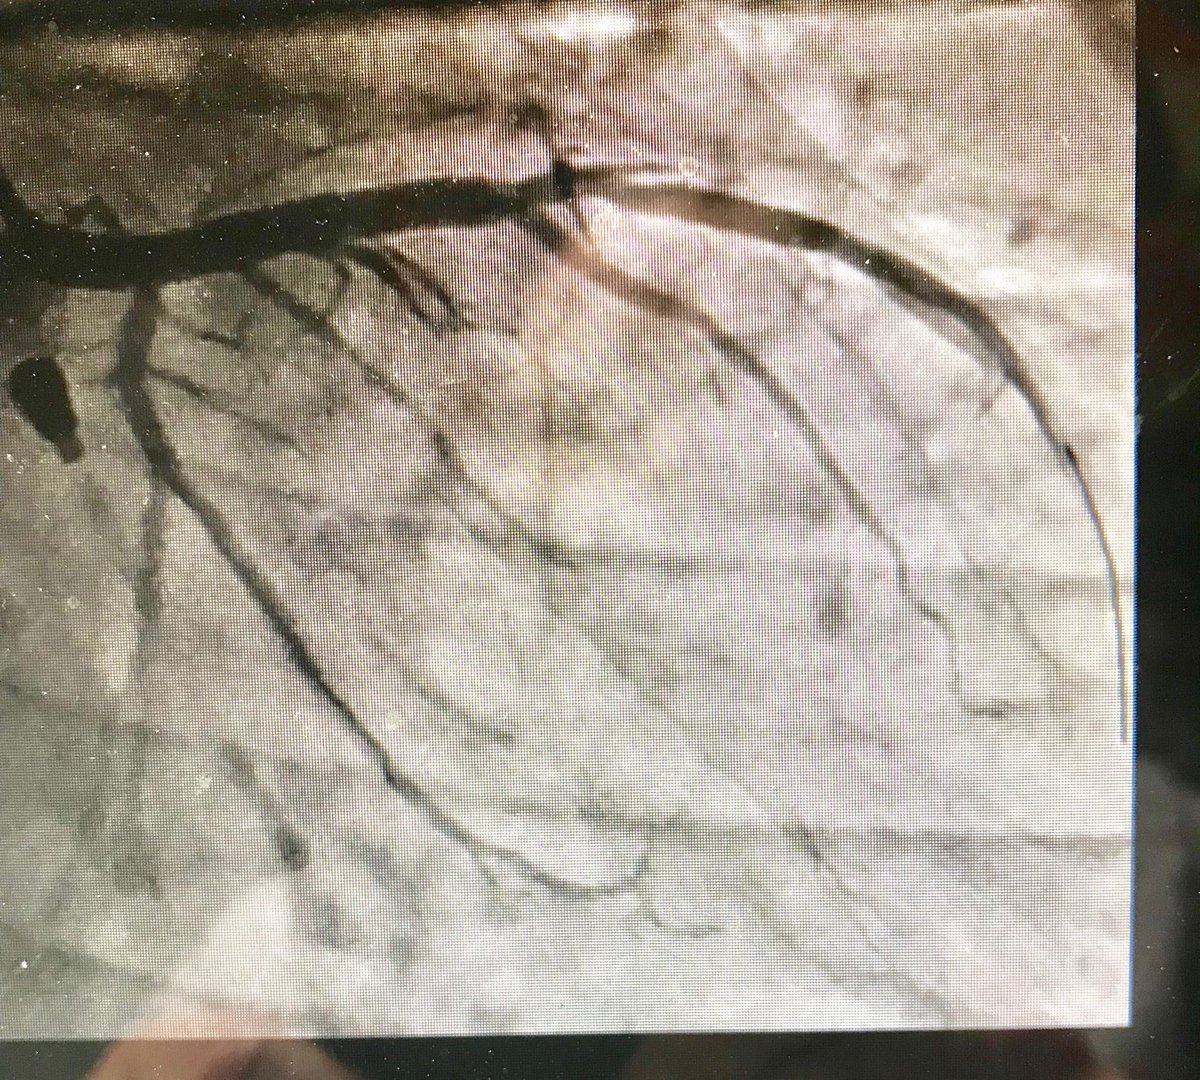

38m cp 30 hrs nstemi #RadialFirst opened LAD, brought back 2 weeks 7f guide #safefemoral #protectedpci #impella #ivus 4.5 DES in LAD>LM. Pot 5.0 #preclose home next day EF now 50

istentem's tweet image. 38m cp 30 hrs nstemi #RadialFirst opened LAD, brought back 2 weeks 7f guide #safefemoral #protectedpci #impella #ivus 4.5 DES in LAD>LM. Pot 5.0 #preclose home next day EF now 50